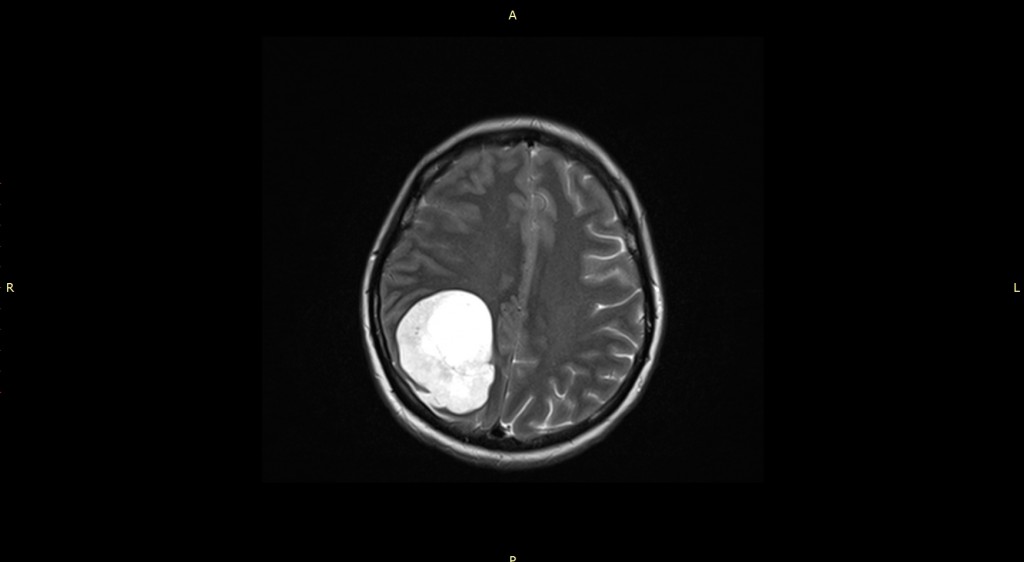

«В пятницу вечером она позвонила мне с жалобами. С учетом трансплантированного сердца и приема иммуносупрессивной терапии, а также онкологического анамнеза, характерна атипичная клиническая картина. Принято решение о ее немедленной госпитализации. В течение часа пациентка была доставлена в Центр Алмазова в сопровождении сестры. Здесь коллеги оперативно выполнили комплексное обследование и были поражены, обнаружив при МРТ головного мозга крупную (6 х 5 х 6 см) опухоль в правом полушарии», — рассказывает врач — кардиолог-трансплантолог клинико-диагностического центра НМИЦ им. В. А. Алмазова Мария Андреевна Симоненко.

На момент поступления у пациентки в неврологическом статусе были выявлены гипертензионный синдром, левосторонняя гемианопсия, легкая статическая атаксия. Консилиум совместно с заведующим отделением нейрохирургии № 5, к.м.н. П. В. Красношлыком и руководителем лаборатории интегративных нейрохирургических технологий, д.м.н. Д. А. Гуляевым, принял решение о проведении хирургического лечения новообразования головного мозга в ускоренные сроки.

8 ноября 2023 года пациентке было выполнено микрохирургическое удаление опухоли правой теменной доли с использованием нейрофизиологического мониторинга. Оперировал врач-нейрохирург профессор Дмитрий Александрович Гуляев.

На следующие сутки после операции больная была переведена из отделения реанимации в палату. Гистологическое исследование подтвердило предполагаемый диагноз: метастаз миксофибросаркомы сердца. Простыми словами, злокачественная опухоль, удаленная вместе с сердцем все-таки, дала метастаз в головной мозг. Стоит отметить, что первичные опухоли сердца встречаются очень редко. При этом миксофибросаркомы составляют менее 1 % от всех опухолей сердца. А вот чтобы рак еще и распространился в мозг – таких случаев в мире единицы.